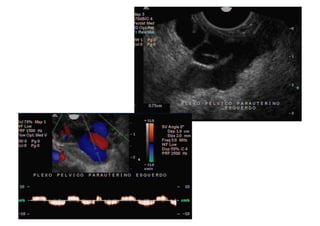

Comment  établir  le  diagnos=que  ?   1.  Par   la   symptomatologie,   en   par8culier   la   douleur  et  la  lourdeur  dans  le  bassin  avec  une   aggrava8on   pendant   la   menstrua8on,   mais   aussi   la   dysménorrhée,   la   dyspareunie,   la   cons8pa8on  et  les  douleurs  lombaires.   2.  Par   la   présence   de   varices   dans   la   région   postérieure   et   latérale   des   cuisses,   dans   les   fessiers  et  les  par=es  génitales.   3.  À   l’aide   d’un   écho-­‐doppler   transvaginal   et   abdominal.

Transfert  de  reflux  vers  les  veines  des   fessiers  et  des  eschios   Transferência  de  Refluxo  pelas    Veias  glúteas      Isquiá8cas